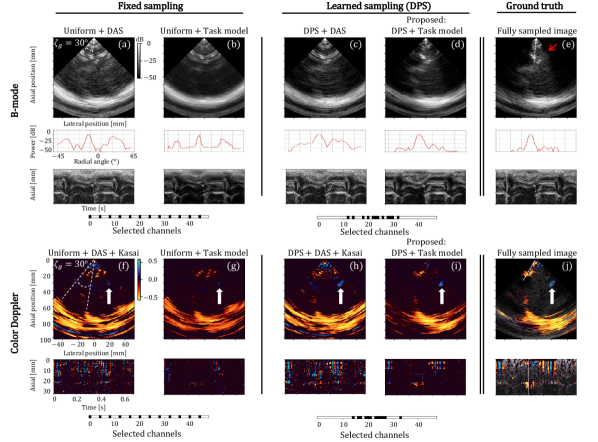

Figure 5: Reconstructed anatomical B- and M-mode (a-e) and color Doppler images (f-j) after sub-sampling by a factor 4 across slow-time frames, either uniformly (a, b, f, g), or learned by DPS (c, d, h, i). For both sampling strategies we compare the jointly learned task model gθ()subscript𝑔𝜃g_{\theta}(\cdot) (b, g, d, i) to a naive non-learned method for the task at hand (cubic interpolation in a and c, followed by the Kasai auto-correlator in f and h). (e, j) Fully sampled images as a reference. For fair comparison, we display a frame that is not sampled by either of the compared sub-sampling strategies (a-i). The dashed lines in the top and bottom image indicate the selected radial M-mode line and B-mode frame, respectively.

Figure 5 demonstrates anatomical B-mode (a-e) and color Doppler (f-j) reconstructions for both fixed uniform and DPS-driven sub-sampled slow-time transmits. For uniform sub-sampling, the DPS block in Fig. 2a is replaced by a (non-trainable) uniform sub-sampling operation. The adopted sampling patterns (with selected frames in black) are visualized below the reconstructions. Note that for DPS, these sampling patterns correspond to a single stochastic realization from the trained probability distributions, on which we detail in Appendix A. To demonstrate both the individual and joint contributions of DPS and the task-model to performance, we moreover compare our trained neural network task model to a non-learned cubic-interpolation-based reconstruction method for both sampling strategies.

Interestingly, DPS’ learned sampling patterns for both tasks showed to be very distinct. For B-mode reconstruction, the learned pattern exhibited an almost perfectly uniform sampling pattern (Fig. 5c and d), whereas For Doppler reconstruction, the sub-sampling pattern found by DPS exhibited an ‘ensemble’-type of sampling (Fig. 5h and i). For both tasks, similar patterns were clearly visible for the other tested sub-sampling factors as well. The learned ‘ensemble’-style sub-sampling pattern for Doppler recovery efficiently captures high frequency slow-time signals due to tissue displacements (Doppler shifts) within ensembles, and relatively low frequency information (changes in Doppler shifts over time) among these ensembles. Given the (nearly) uniform sampling pattern learned by DPS for B-mode reconstruction, the resulting reconstructions using fixed uniform versus learned sub-sampling (Fig. 5a, b and 5c, d, respectively), were found to be similar. For increasing factors, reconstructed images displayed increased blurring for all sampling-reconstruction combinations. The MSEs for different sub-sampling factors, both for uniform and learned sampling by DPS combined with task model gθ()subscript𝑔𝜃g_{\theta}(\cdot), are visualized in Fig. 6a. It confirms the similarity of reconstructed B-mode images for uniform and learned sub-sampling patterns.

The need for accompanying DPS with a jointly trained nonlinear task model becomes particularly evident when comparing the Doppler reconstructions in Fig. 5h and i. Simply interpolating frames and using a standard Doppler estimator (Kasai) leads to significant aliasing in Fig. 5h. For anatomical B-mode imaging, which does not rely on inter-frame processing, the difference between reconstruction methods mainly manifests itself by the inherent denoising priors of the chosen convolutional architecture.

That joint training of sampling and a dedicated task model yields best results can also be seen in Fig. 6b, where we quantitatively compare fixed versus learned sampling.